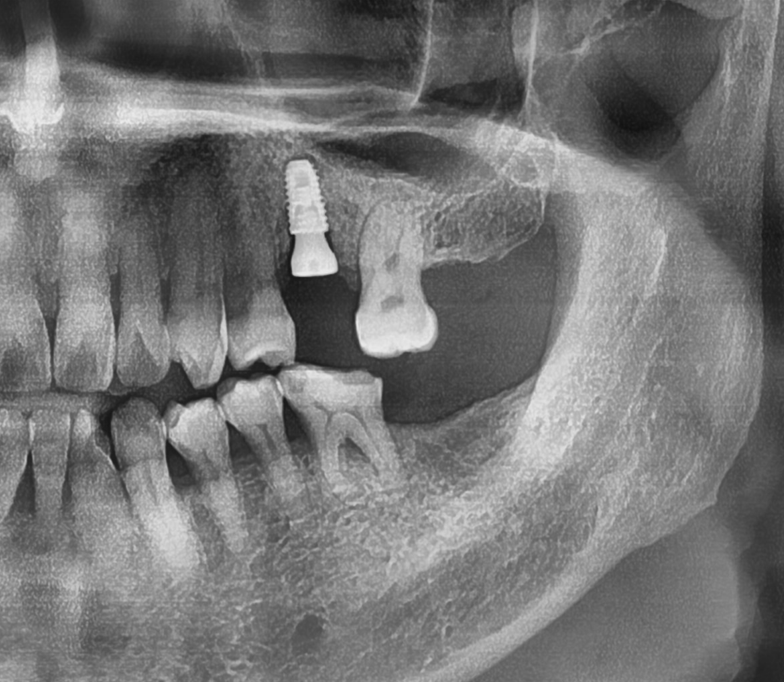

시간이 또 대략 2개월 가량이 흘러서 이렇게 지르코니아 크라운까지 시적을 해드리면

반대편 또한 고정체 1개를 심어드리게 됩니다. 물론, 여기에도 상악동 거상술 은

진행했었습니다.